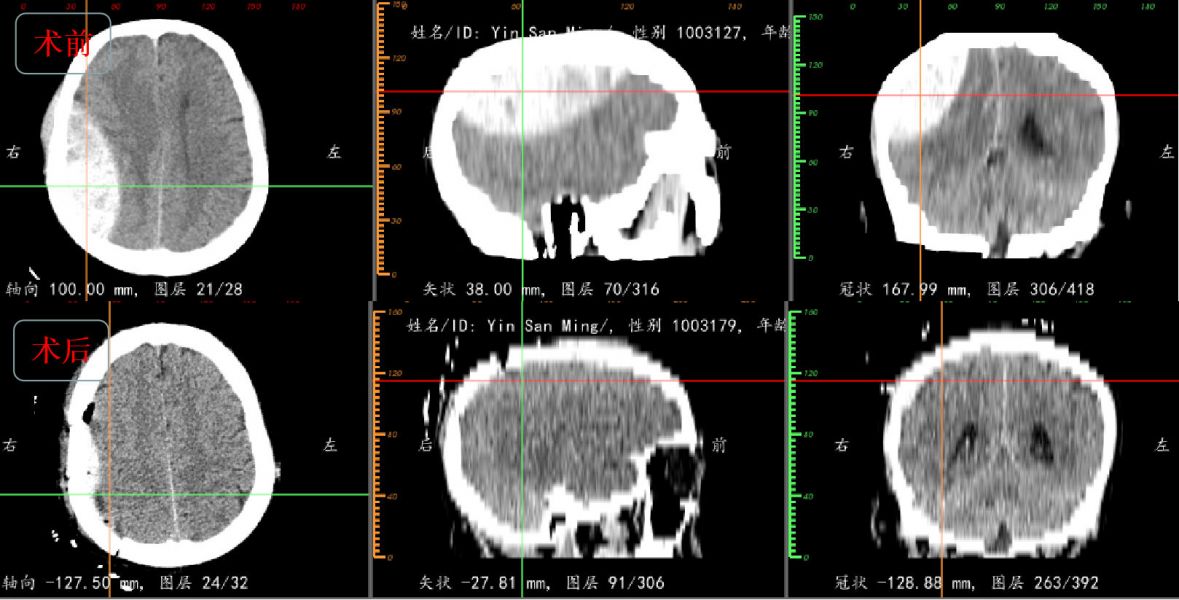

56岁患者尹某,因外伤后头痛伴意识障碍进行性加重3小时,于8月3日23:04入院。入院查体:血压124/88mmHg,意识模糊不清,GCS评分10分,言语含糊,不能正确对答,右侧额顶部头皮肿胀,双侧瞳孔等大等圆,直径约3mm,张口伸舌不能合作,左侧肢体偏瘫,刺痛反应差。急诊行颅脑CT提示右侧颞顶骨线性骨折并巨大硬膜外血肿,初步估算血肿量约100ml。

得益于精准的定位及术前的模拟,最终手术历时1.5小时,顺利清除血肿并回纳骨瓣,术后患者意识及偏瘫肢体肌力明显好转,避免了神经功能的持续恶化。

据神经外一科向昌华主任介绍:外伤性硬膜外血肿(Epidural Hematoma,EDH)常见部位在颞部或颞顶部,该处颅骨较薄易在外力作用下发生骨折;其次颞部是脑膜中动脉主干及分支所在部位,也有来自静脉或骨折缝的出血。单纯EDH手术治疗往往能取得良好的疗效。手术根据血肿大小、部位制定相应的手术切口及骨窗大小,手术以清除血肿为目的,操作时要保护血肿下方静脉窦、脑皮层,避免操作损伤。利用E3D处理该类患者具有以下优势:(1)载入轴位图像能自动生成矢状位和冠状位图像,将患者二维影像转化成三维影像,并能提供距离、面积、体积等定量参数,便于全面获取血肿信息;(2)利用三维重建技术,能方便直观的判断血肿所在位置,与骨折缝、中线的空间关系,有助于准确定位;(3)颅脑的三维可视化效果可以很直观地判断脑组织受压程度,使解剖变得直观,便于制定手术计划和术中预警。